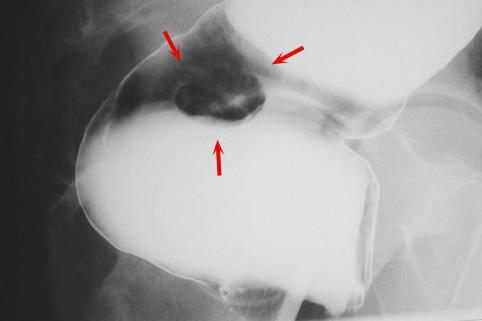

질환(병리주체)의 분류 카시노이드종양/

부위(장기별) 대장/직장

검사방법 X-P

종양의 최대경(밀리미터) 15~19